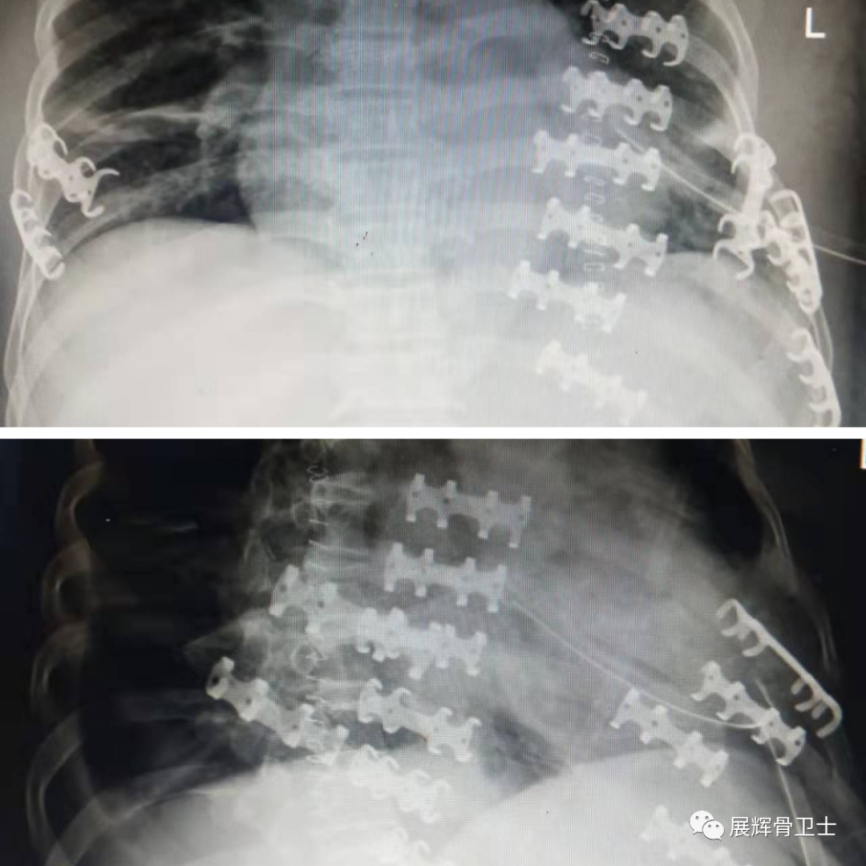

术后影像